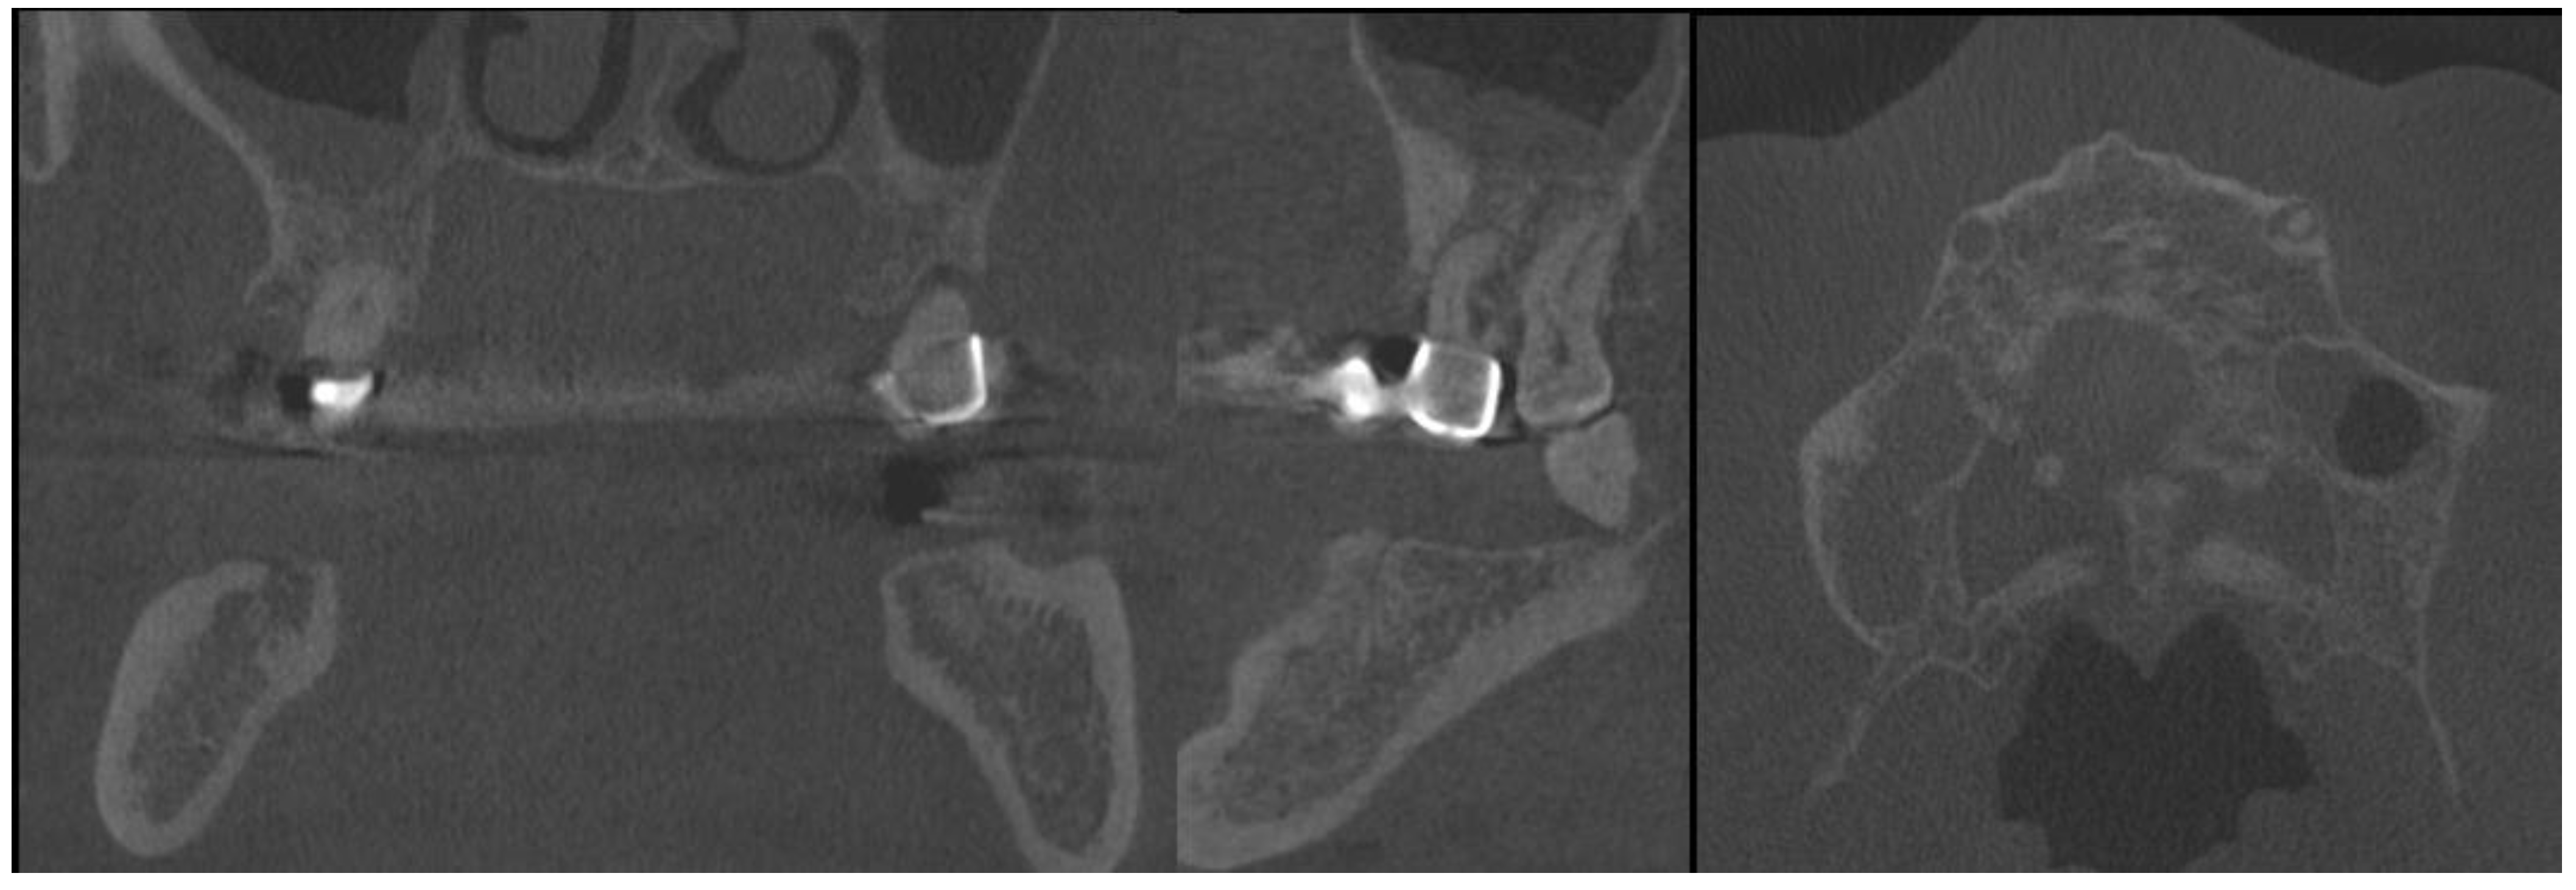

2. Case Description